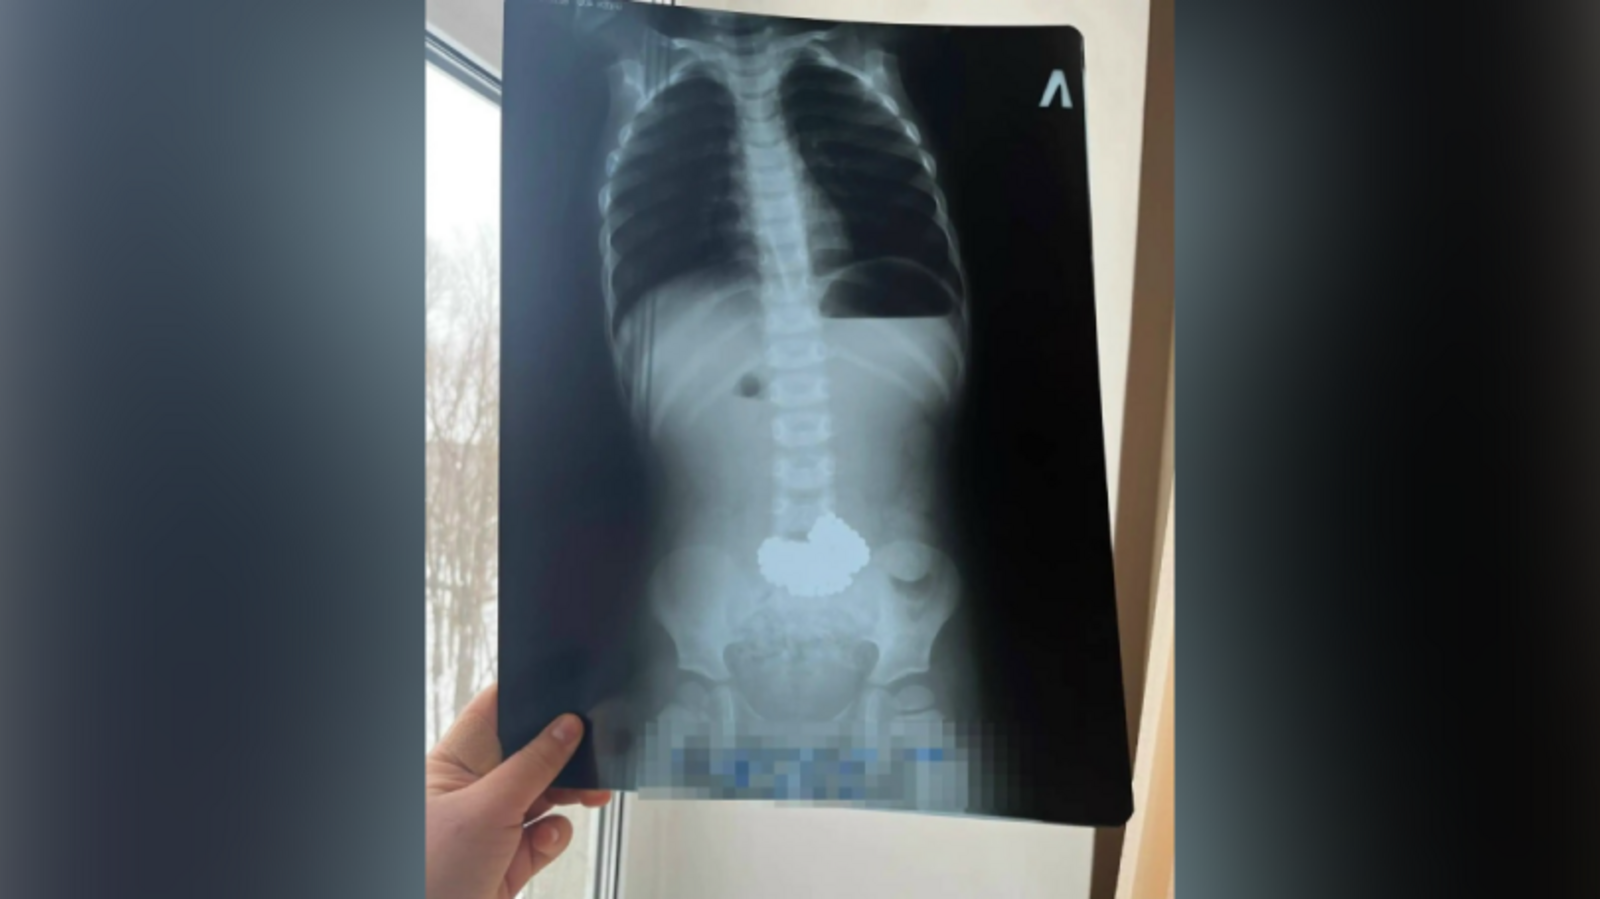

В Башкирии трёхлетний ребёнок проглотил 206 магнитных шариков

Ребенок увлекался игрой с металлическими шариками и решил провести необычный эксперимент. Родители обнаружили исчезновение игрушек лишь спустя некоторое время, когда ситуация стала критической.

Мальчика немедленно доставили в ближайшую медицинскую организацию, откуда экстренно переправили санитарной авиацией в Республиканскую детскую клиническую больницу города Уфа. Здесь хирурги оперативно провели хирургическое вмешательство и осторожно извлекли металлические предметы. Теперь состояние маленького пациента стабилизировалось, угрозы здоровью больше нет.

Фото: городская больница Нефтекамска.